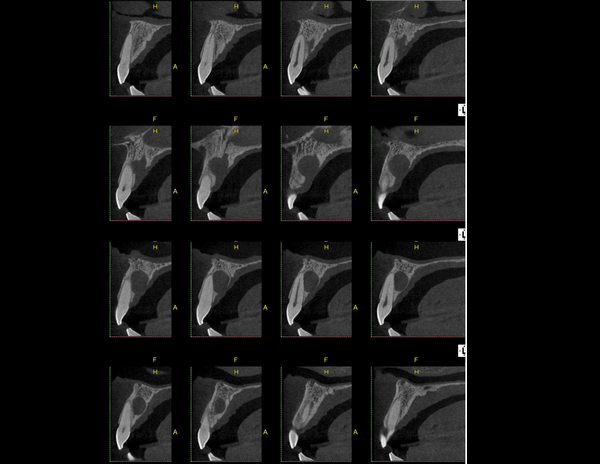

A Tomografia Computadorizada pela técnica do feixe cônico/cone beam (CBCT) introduziu um novo conceito de tomografia computadorizada na região bucomaxilofacial, que por meio da rápida aquisição volumétrica produz imagens com altíssimo grau de definição e fidelidade, além da redução na dose total de radiação emitida ao paciente.

Além disso, ocorre a minimização dos artefatos de imagem em relação à TC médica, o que torna possível a realização de imagens com qualidade diagnóstica e precisão sub-milimétrica, mesmo na presença de estruturas metálicas (restaurações, pinos/núcleos, aparelhos ortodônticos).